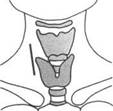

T2-BH(FATSAT).